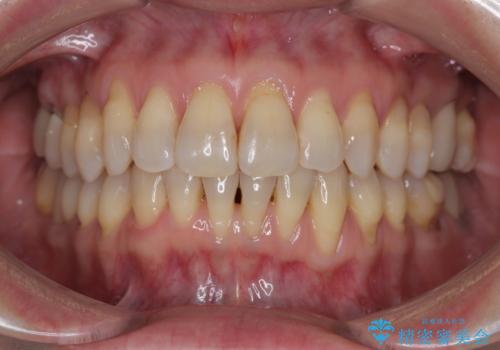

前歯のデコボコと突出感をマウスピース矯正できれいに